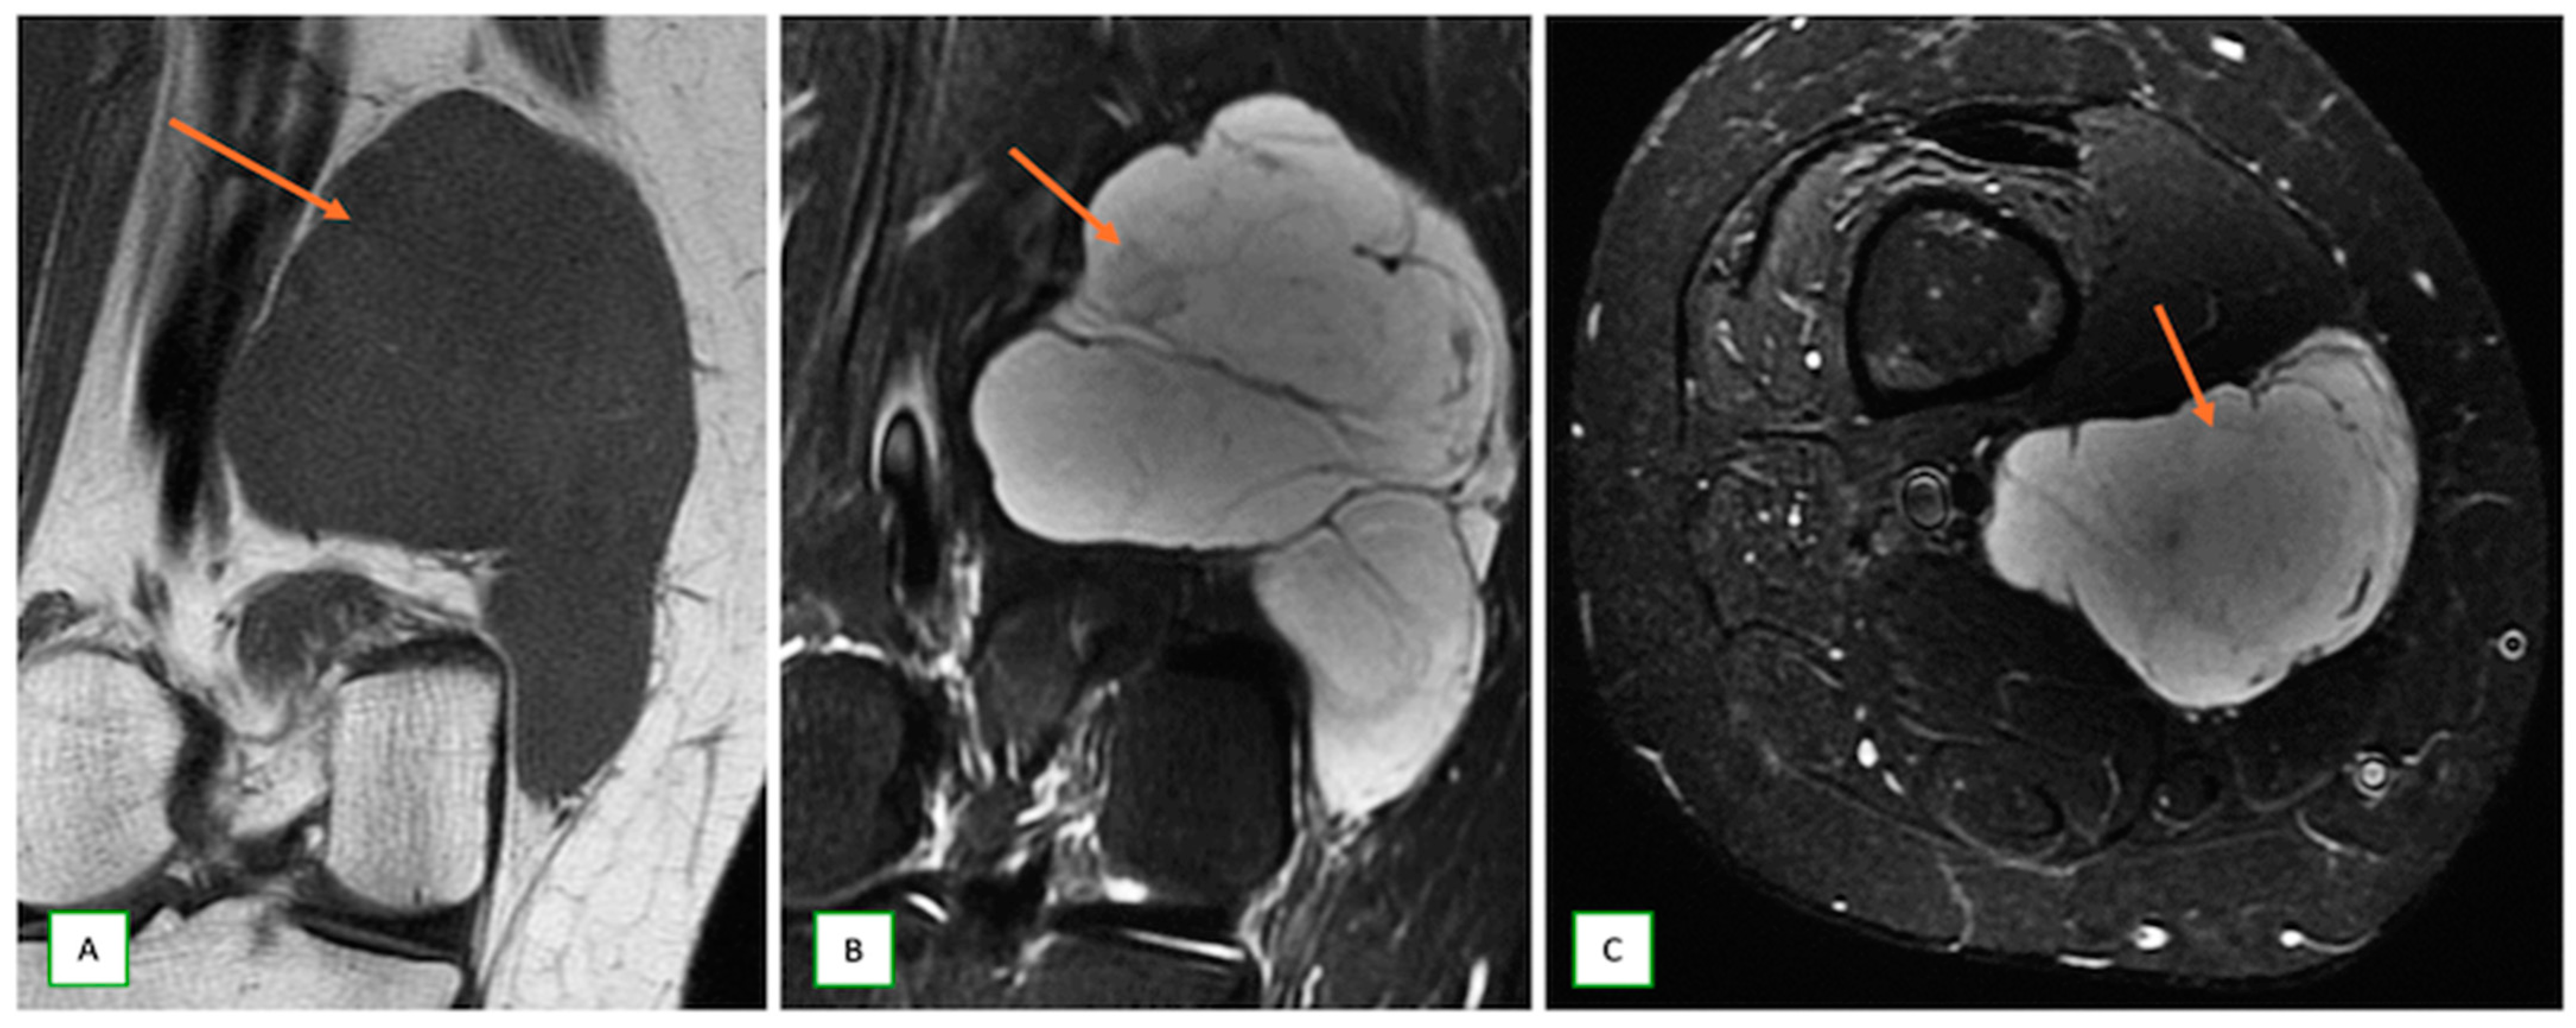

- Primary Sarcomas: Soft-tissue sarcomas are uncommon, accounting for just over 1% of adult malignancies. Synovial sarcoma, clear cell sarcoma, and epithelioid sarcomas are known to involve peripheral nerves. CT/MR reveals a large soft tissue mass with areas of necrosis or calcification and heterogeneous contrast enhancement. F-18 FDG uptake is useful for both tumor staging and treatment assessment (Figure 26, Figure 27 and Figure 28).